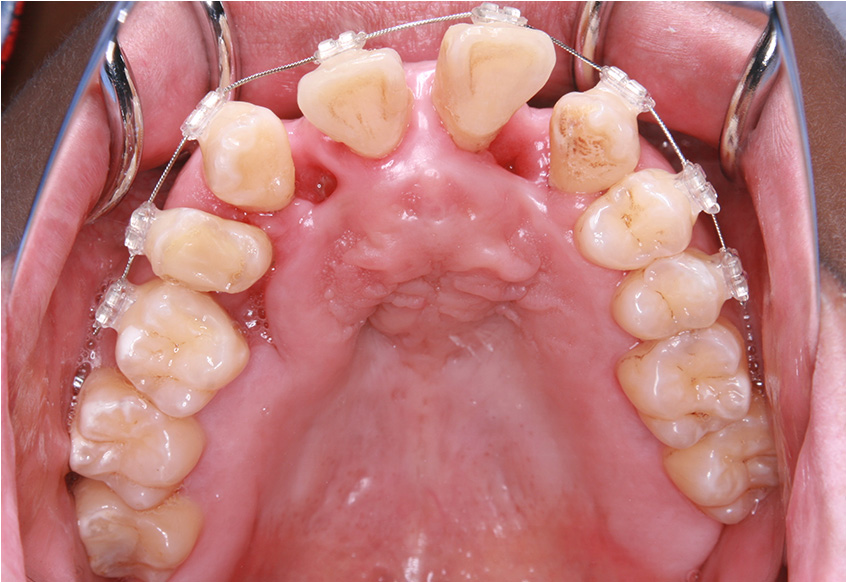

最初のお口の中 ワイヤー装着して治療を開始

-

| 治療内容 | 上顎側切歯を2本抜歯した後、上顎の歯にブラケットを装着し、ワイヤー、矯正用ゴムで歯の移動を行いました。その後、被せ物の治療を行って治療を終了しています。 |